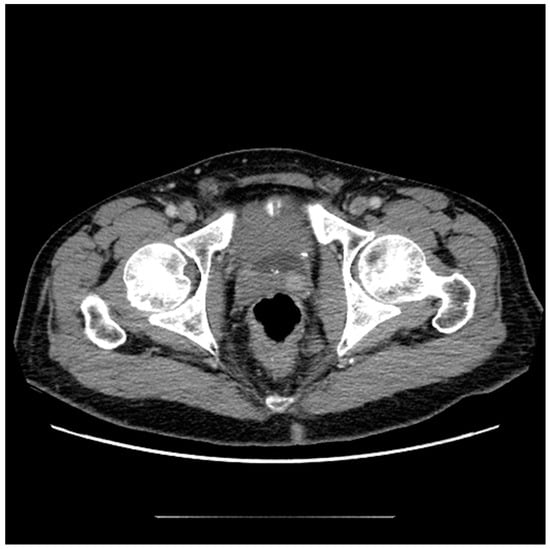

It is widely accepted that CT is insufficient for the diagnosis and monitoring of prostate cancer within the gland due to its inferior soft tissue characterization [6]. The relatively high radiation dose associated with this modality also limits its use as a screening tool. However, although other modalities outperform CT in the diagnostic workup of prostate cancer, it may still have a role. Additionally, with the emerging field of radiomics, additional information can be extracted from CT scans that is not readily apparent in conventional imaging [7,8]. Due to the fact that CT scans are so widely available and frequently performed, familiarity with the appearance and limitations of prostate imaging using CT is useful in order to maximize incidental detection of cancers and inform possible next steps [9]. The ability of CT to identify prostate malignancy depends greatly on the location of the lesion within the gland, as BPH nodules within the transition zone are largely indistinguishable from cancers. For example, in one study, helical CT accurately revealed 58% of the cancer sites in the peripheral zone, whereas nodules in the transition zone were indistinguishable from benign change [10]. Another study showed that although CT was insensitive for the detection of prostate cancer (17.4%), when lesions were considered highly suspicious when using CT, it was 98% specific for malignancy, adding further evidence that suspicious CT lesions warrant further investigation [9]. Additionally, of twenty MRIs with lesions suspicious for clinically significant prostate cancer, fifteen had an accompanying CT correlate of focal intraprostatic hyperenhancement (Figure 1) [5].

Figure 1. Axial CT image of the pelvis following the administration of intravenous contrast demonstrates focal asymmetric enhancement of the left seminal vesicle, subsequently found to represent prostate cancer at the time of biopsy.